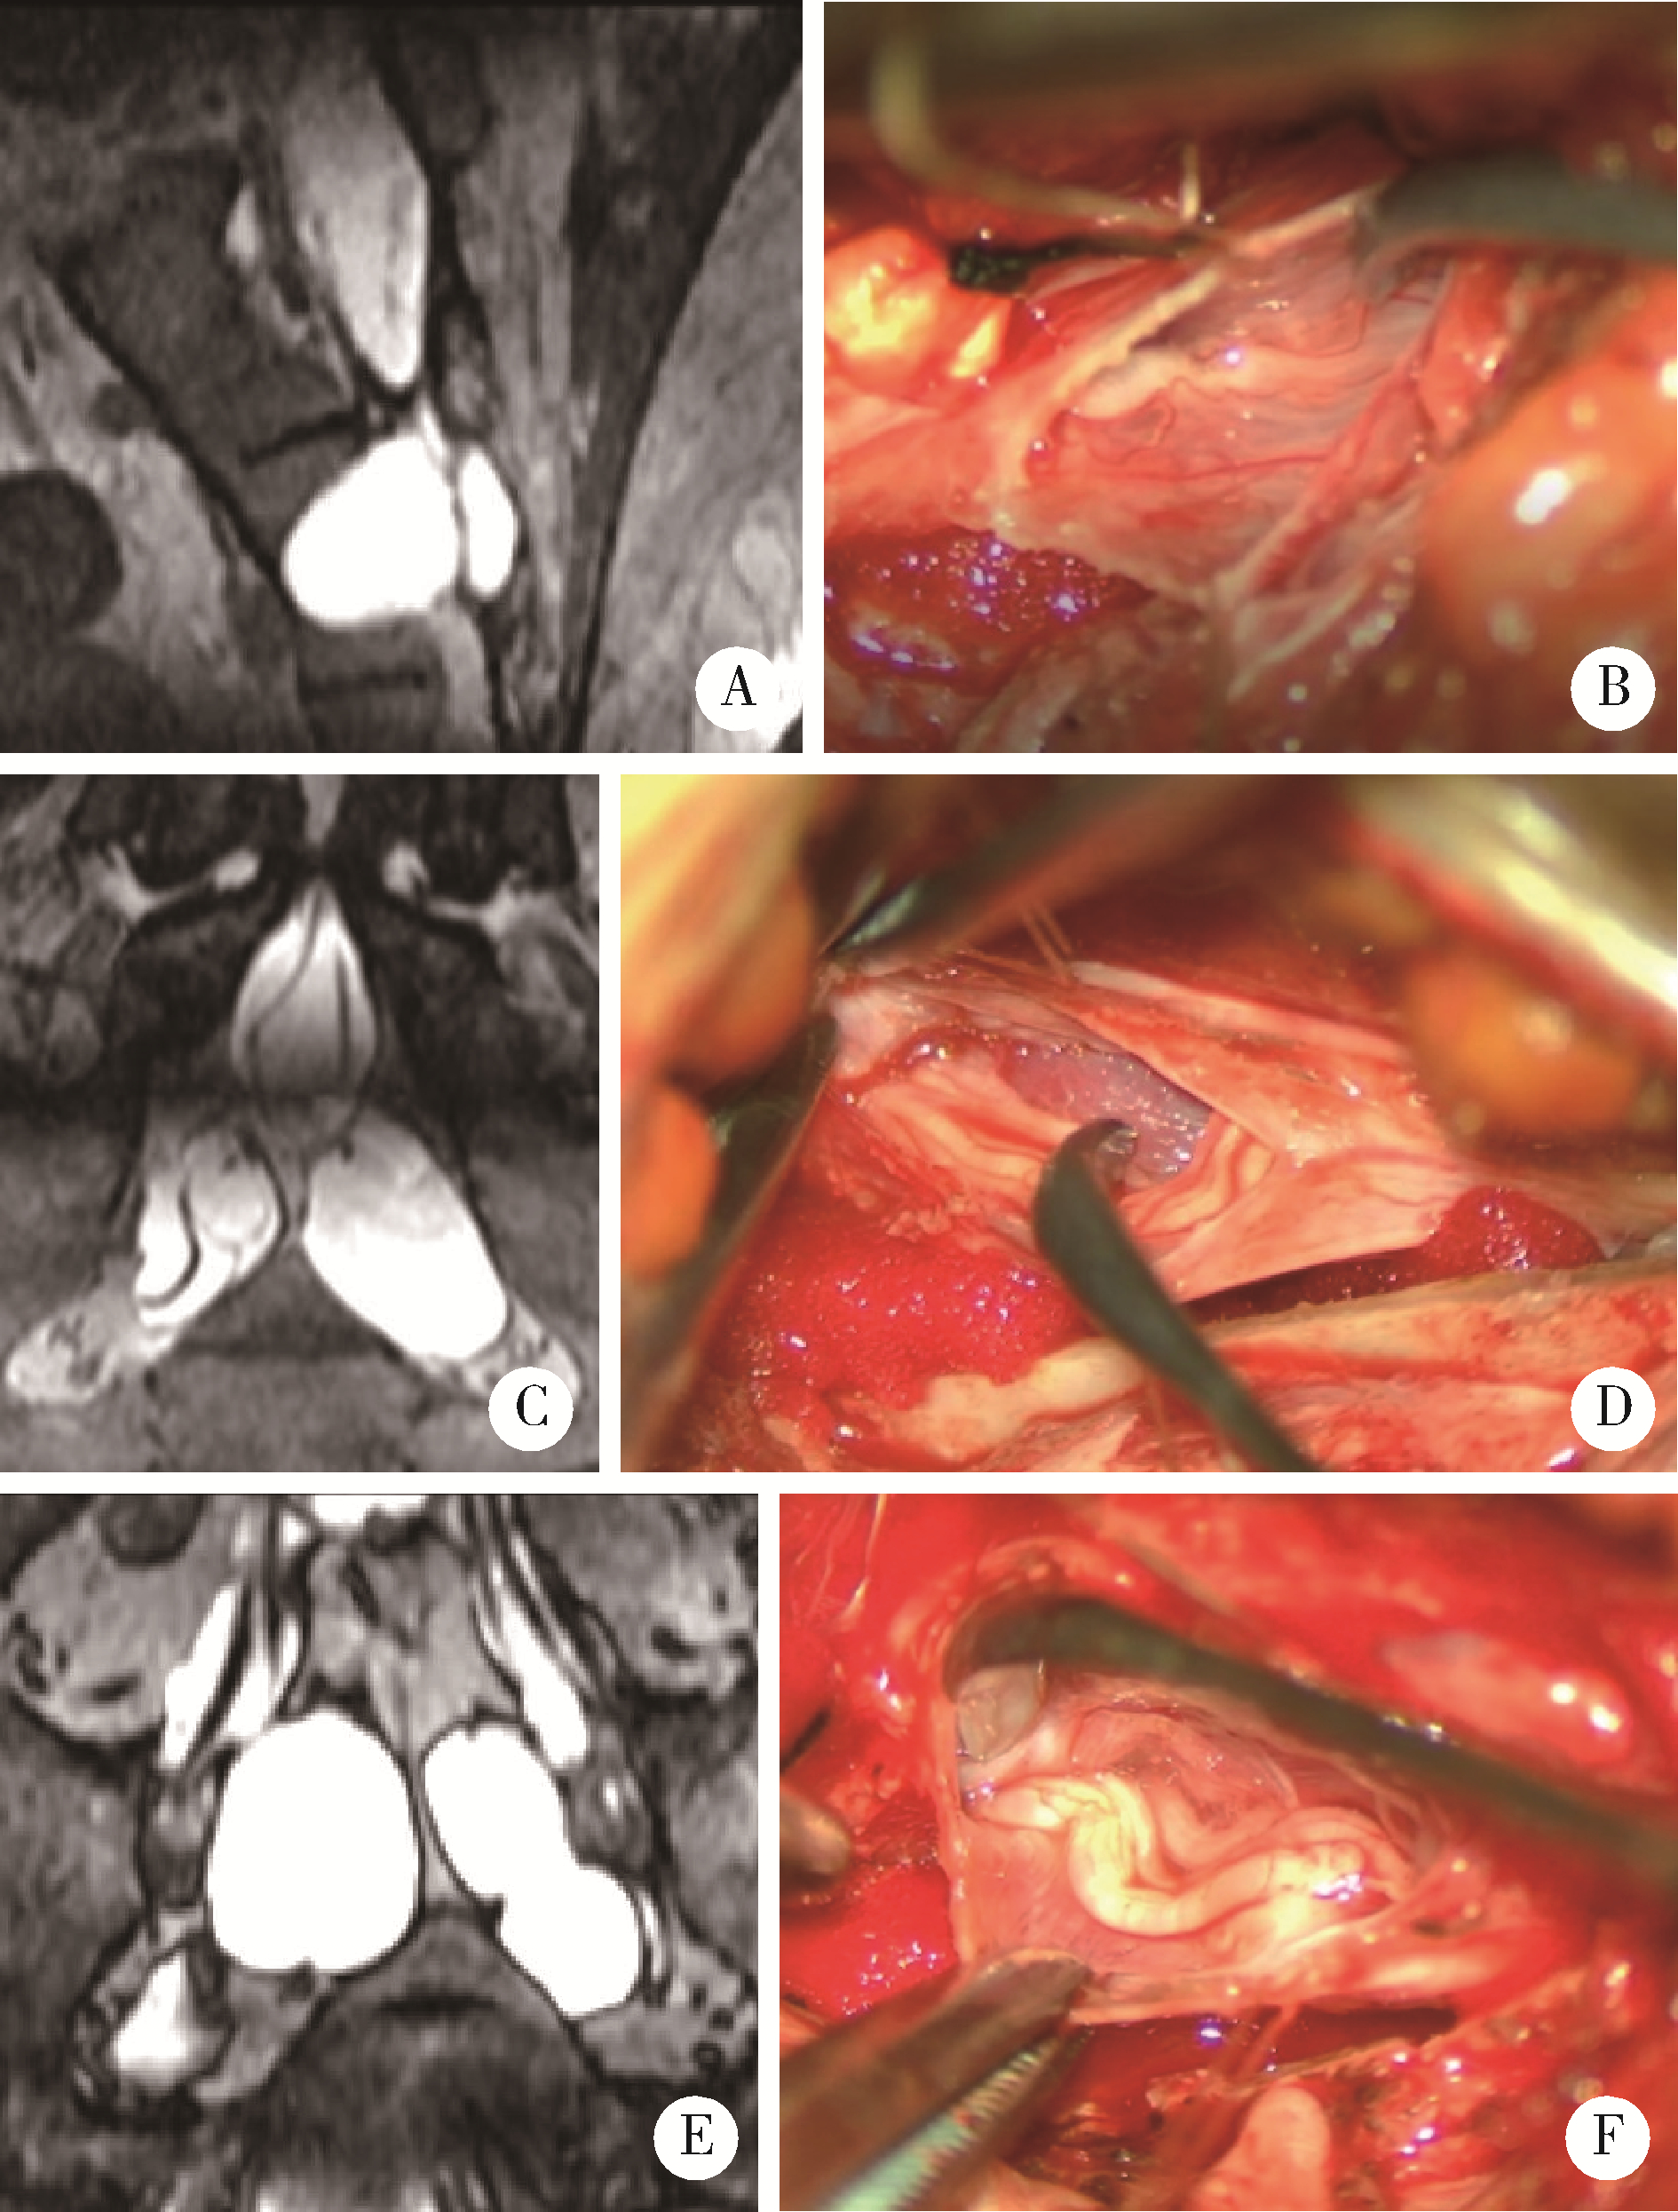

图2

内无神经根型骶管囊肿的各种类型"